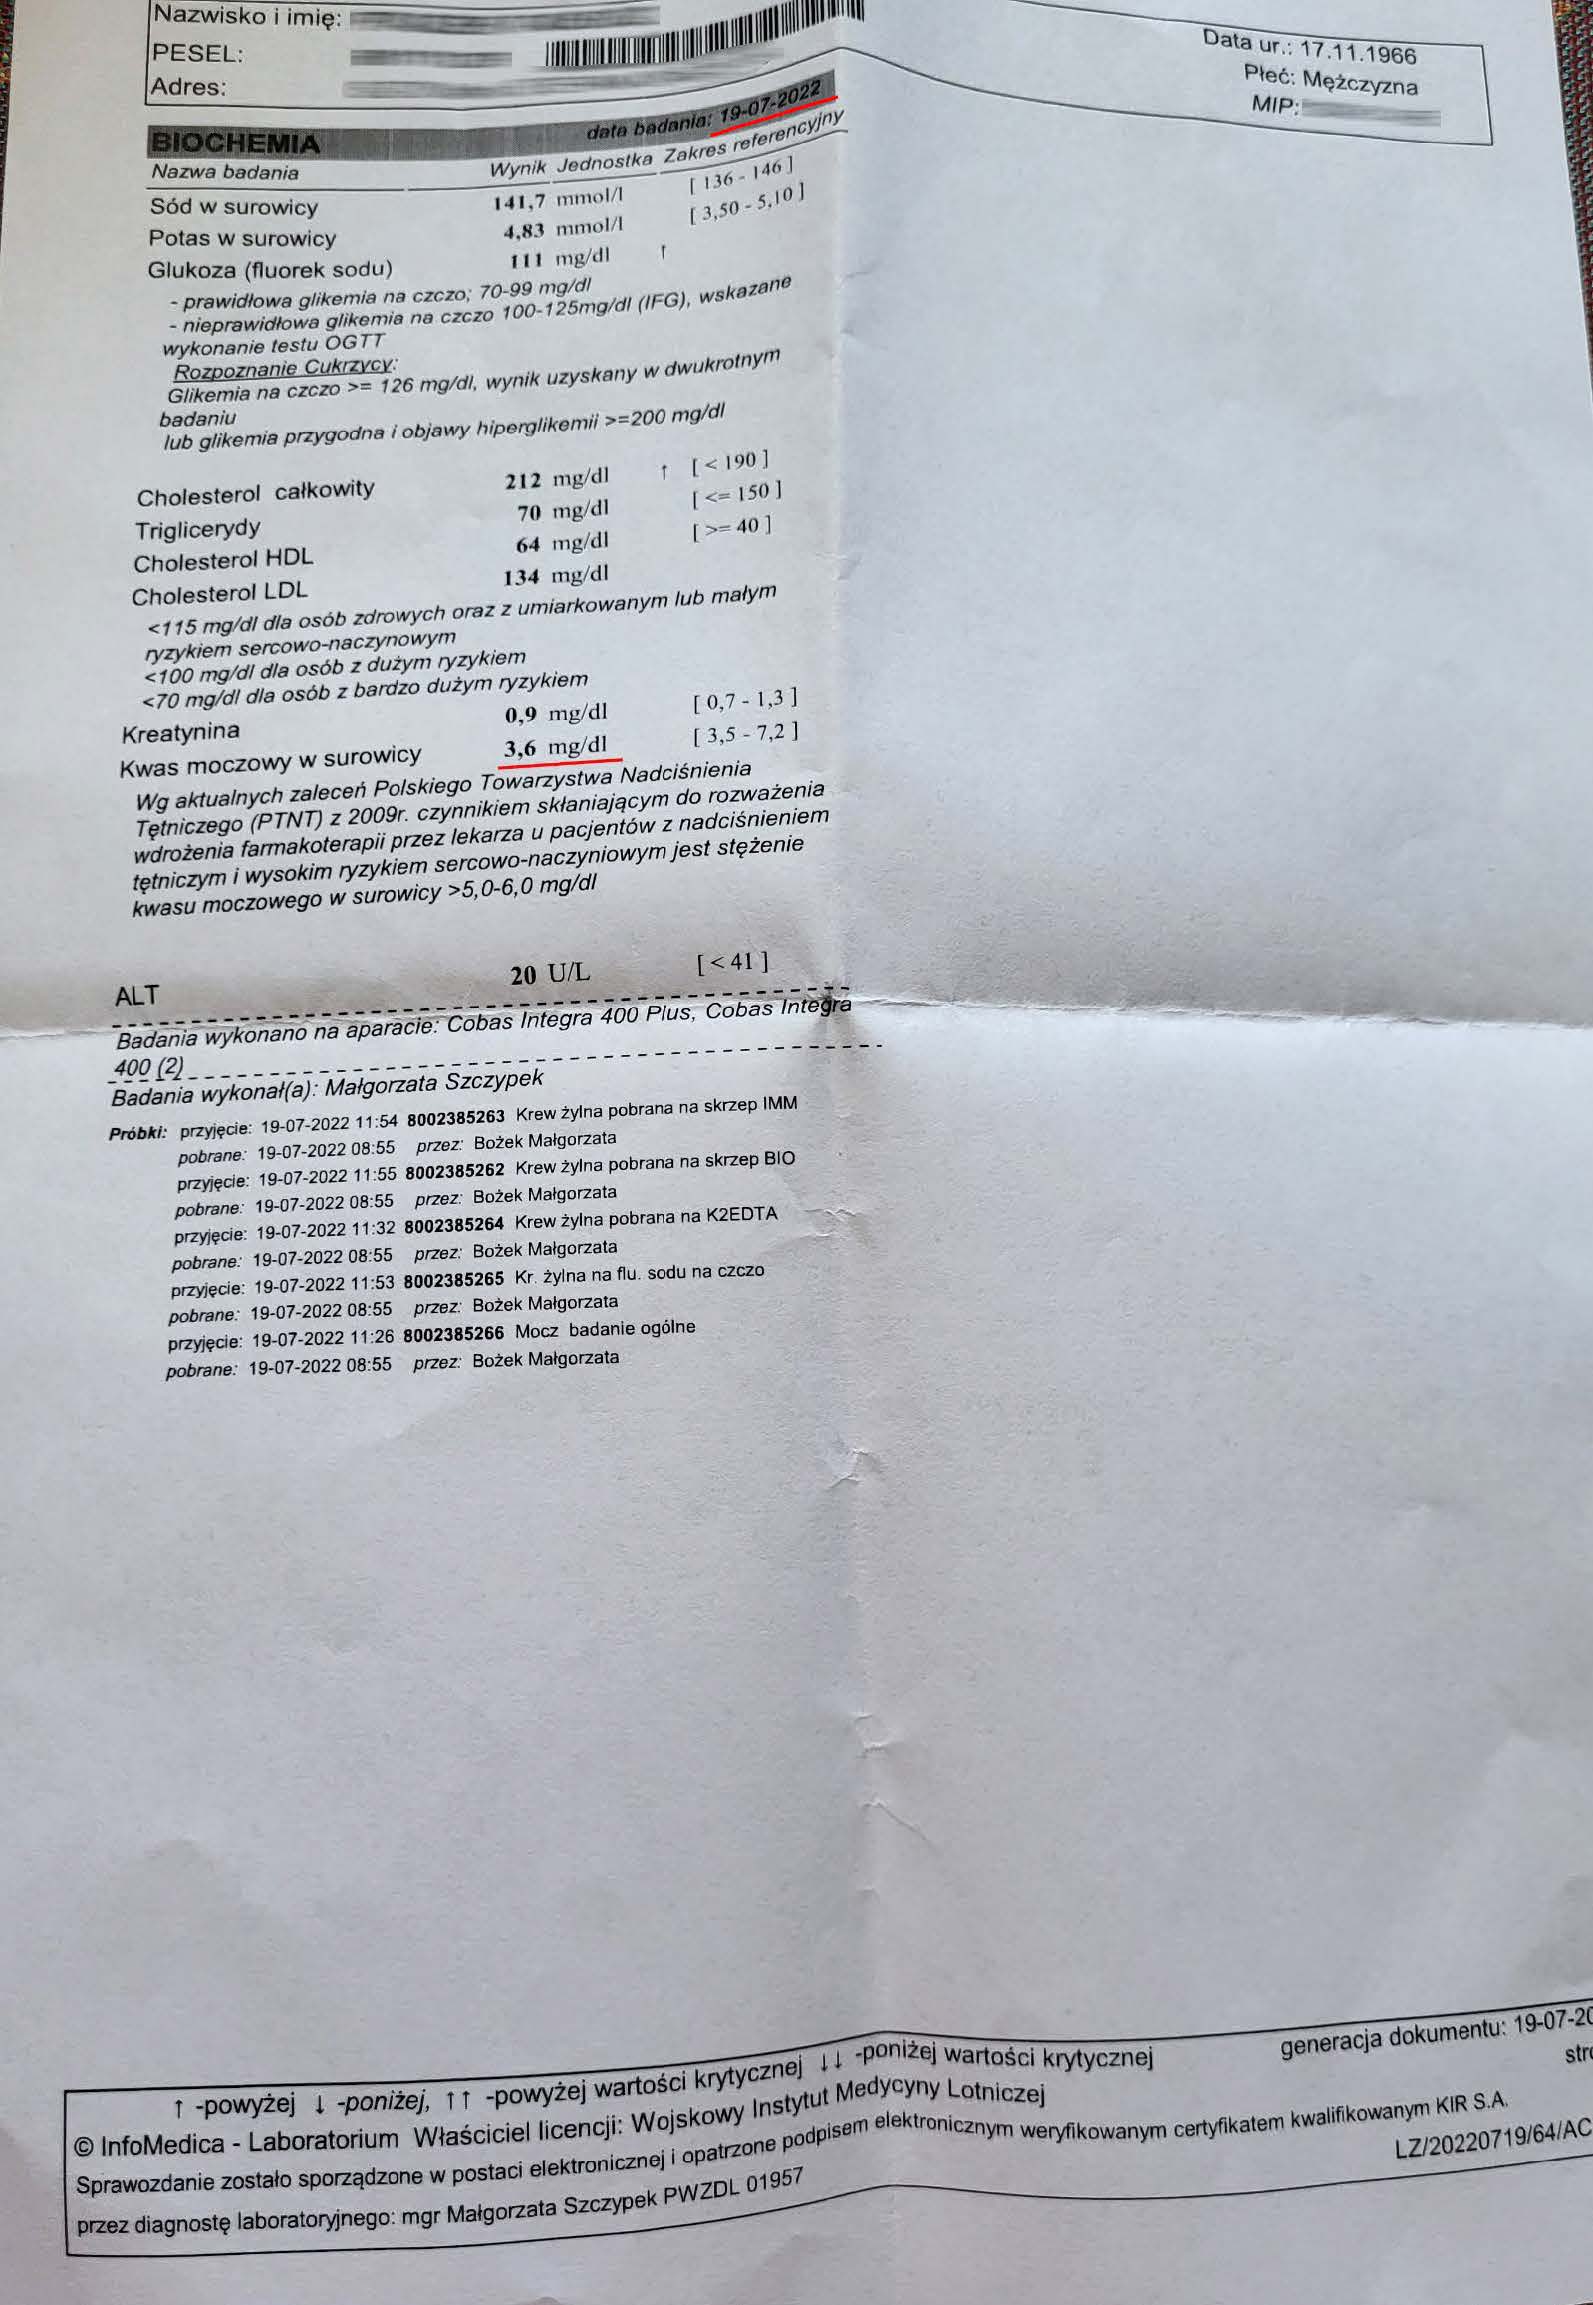

EFEKT PREPARATU NA PODAGRĘ

Dna moczanowa u 56 letniego mężczyzny, diametralny spadek kwasu moczowego. Wartość przed terapią 9,0 mg/dl towarzyszące cykliczne ataki dny , historia choroby zaczęła się jednak znacznie wcześniej niż data pierwszego badania. W roku 2022 rozpoczęto terapię preparatem i po 3 miesiącach stosowania odnotowano spadek kwasu moczowego do 7,9 mg/dl , natomiast po stosowaniu przez następne 6 miesięcy ilość kwasu moczowego obniżona została do poziomu 3,6 mg/dl, wraz z obniżeniem poziomu kwasu moczowego do pożądanego poziomu ustały ataki dny, efekt utrzymuje się trwale. Redukcja o 60% kwasu moczowego pokazuje odwrócenie nagromadzeń moczanowych. Preparat zwiększa ATP mitochondrialny w komórkach nerek i wątroby, poprawiając metabolizm puryn i filtrację, co usuwa kryształy moczanu i wycofuje zapalenie stawów. Standardowe leczenie allopurynolem i kolchicyną wymaga dożywotniego leczenia obarczonego skutkami ubocznymi, które wpływają na codzienne funkcjonowanie, w przypadku preparatu brak skutków ubocznych i relatywnie szybka odpowiedź organizmu.